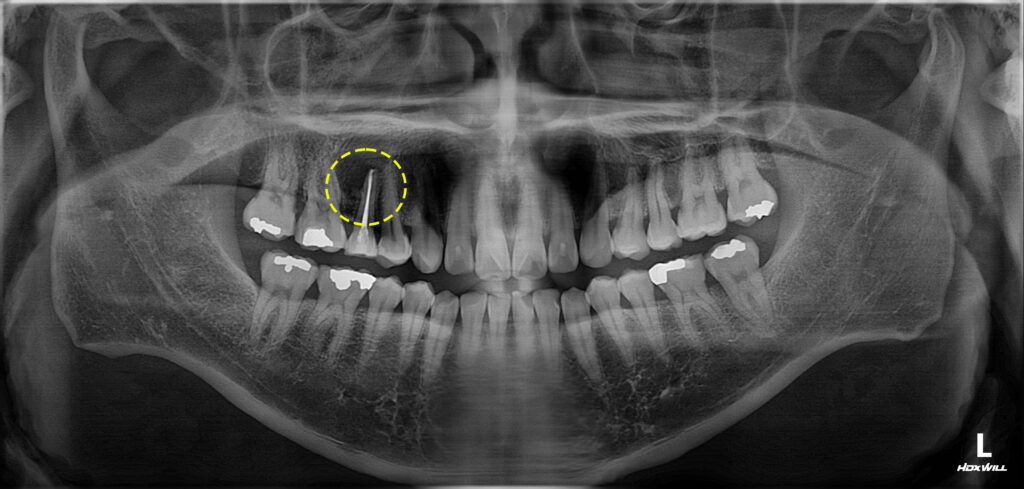

환자분께서는 신경치료 후 크라운을

진행하지 않았던 오른쪽 위 작은 어금니

뿌리의 큰 낭종이 생겨 있는 상태였는데요.

위턱뼈의 3개 치아가 넘는 크기의

낭종으로 제거가 필요한 상황임을

설명드리고 치료 계획을 수립하였습니다.